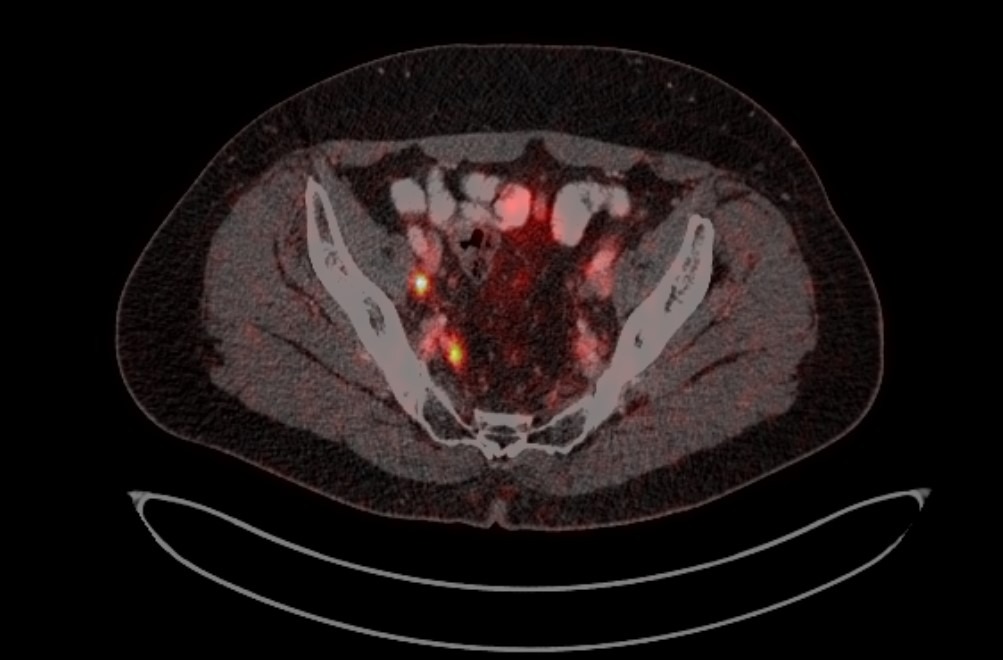

Рис. 4. ПЭТ-КТ изображения больного М. с поражением тазовых лимфоузлов

Рис. 3. Пути распространения рака предстательной железы в лимфоузлы таза.